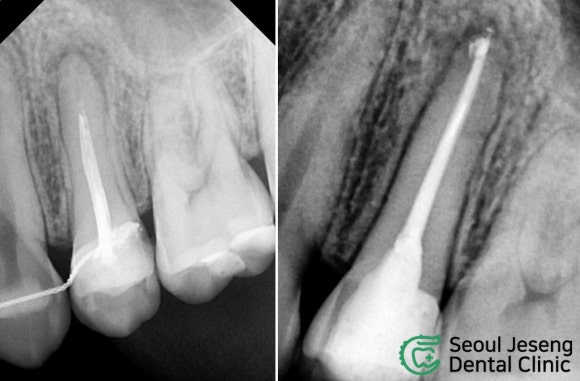

서울재생치과의원 신촌본원의 네이버 블로그 원문을 보존한 아카이브 페이지입니다. 치료사례/생생후기 카테고리의 [치료사례] 재신경치료 (4) 글을 통해 병원의 한국어 정보 제공 방식과 진료 관련 안내 톤을 확인할 수 있습니다.

#재신경치료 #미세현미경신경치료 #자연치아살리기 #치과보존과전문의 #신촌치과 #신촌서울재생치과